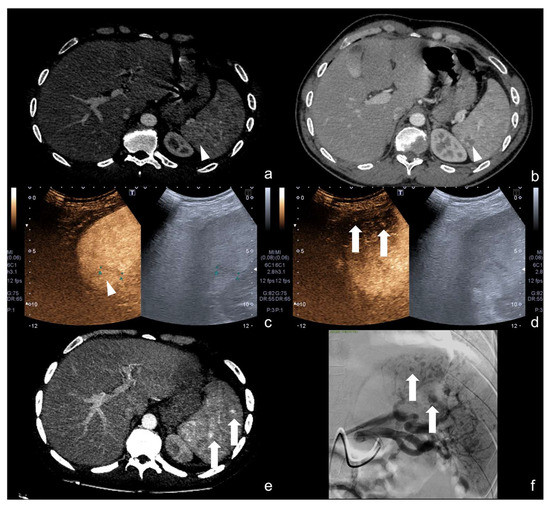

“Turn on the light”: CEUS is more sensitive than US for the detection of solid organ injuries (Figure 23).

Figure 23.

Sub-Glissonian hepatic hematoma in a 40−year-old woman. At B-mode US study (a,b, split image on the left), no definite hematomas was showed. At CEUS evaluation (a,b, split image on the right), the presence of a small sub-Glissonian hematoma was clearly delineated (arrow). Contrast-enhanced CT examination (c, axial and d, coronal view) confirmed the presence of the small non-bleeding sub-Glissonian hematoma (arrow).

4.3. Step 3

An example of multimodal visualization of post-traumatic splenic PSA (white arrows) at CD–US (a), CEUS (b), and arterial phase contrast-enhanced CT scan (c); CEUS follow-up examination after embolization (d) showed no evidence of residual PSA.

Figure 25.

Splenic trauma in car accident with small splenic laceration visible on contrast-enhanced CT scan performed at emergency department (a,b, white arrowhead). CEUS examination performed 4 days after trauma confirmed the splenic laceration (c, white arrowhead); subsequent Flash mode CEUS (d) revealed multiple, small and diffuse intra-splenic PSAs (white arrows) not shown at admission arterial phase CT exam (a); these findings were confirmed at contrast enhanced CT scan (e, arrows) and angiography (f, arrows).